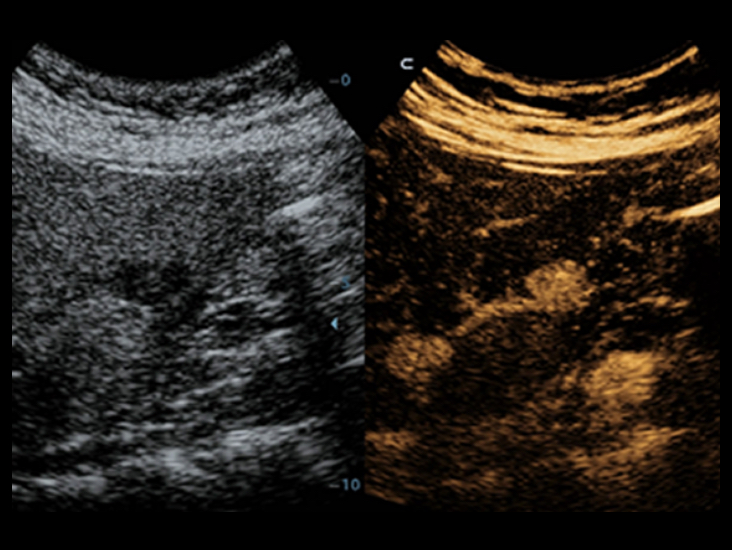

ComboWave

Im Vergleich zu herk?mmlichen Linear-Schallk?pfen verwenden ComboWave-Schallsonden einen piezoelektrischenVerbundwerkstoff. Damit gelingt es, das akustische Spektrum gezielt zu optimieren und die Impedanz zu reduzieren.